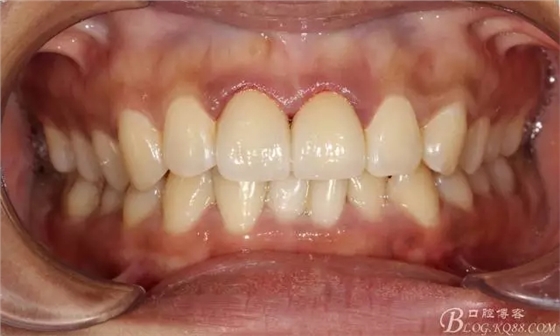

兩周后復(fù)查(訴11遇冷有點(diǎn)不適,因11備牙有點(diǎn)多,露牙本質(zhì)。囑注意不要進(jìn)食過冷過熱食物。癥狀約一個(gè)月后逐漸消失。)

兩周復(fù)查局部放大

復(fù)查舌側(cè)照